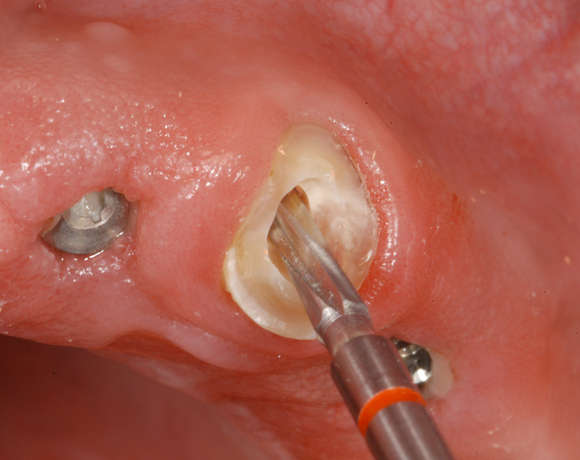

Im nachfolgenden Patientenfall wird ein Zahn mit einem Stift soweit aufgebaut, dass es möglich wird ihn wieder mit einer Krone zu versorgen.